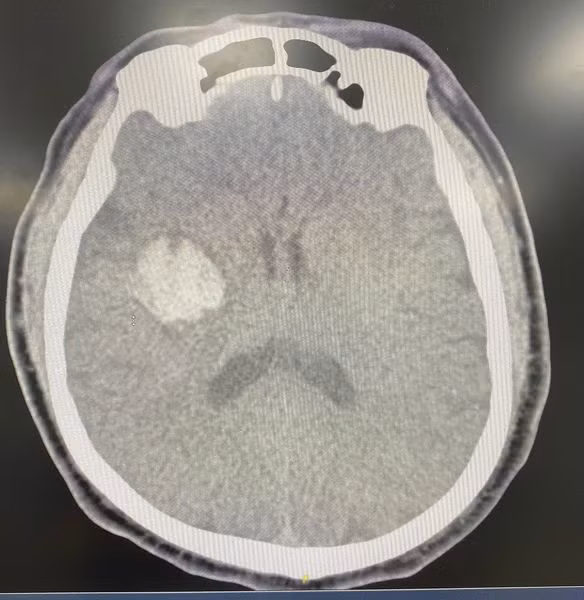

Sau khi uống thuốc các triệu chứng không cải thiện, thậm chí còn có biểu hiện nặng hơn. Người bệnh vào Khoa Cấp cứu – Bệnh viện TWQĐ 108 chụp cắt lớp vi tính sọ não dựng hình mạch máu não (CTA), kết quả cho thấy hình ảnh xuất huyết não vùng nhân xám trung ương phải, không có bất thường mạch máu não.

| Hình ảnh xuất huyết não trên phim chụp - Ảnh BVCC |